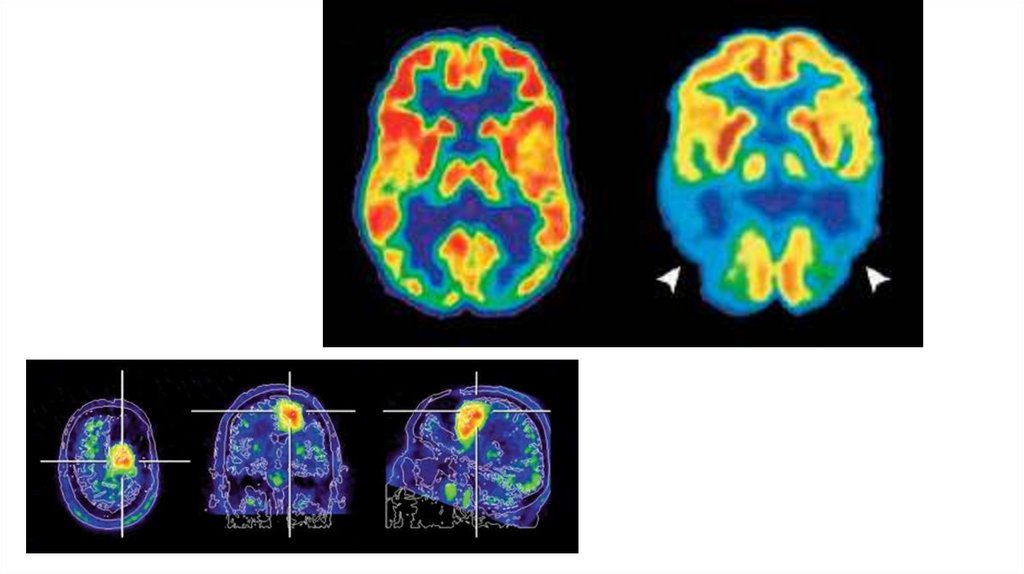

ПЭТ

Преимущества ПЭТ

-

Ранняя диагностика по функции

Информация о метаболической активности

Недостатки ПЭТ

Ионизирующее излучение

Высокая стоимость и сложность

Низкое разрешение деталей